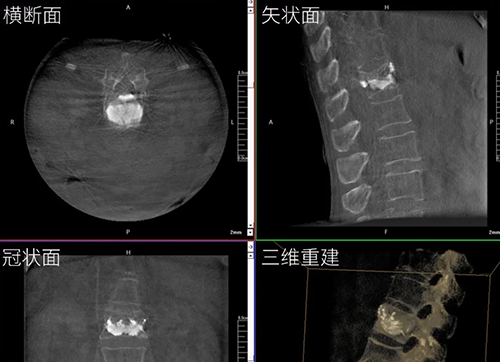

三維C形臂與二維C形臂臨床圖像實時對比

移動式C形臂X射線機有著二維和三維之分,它們都具備透視與攝影功能,能夠為醫(yī)生提供術(shù)中影像引導。三維C形臂采集的圖像究竟比二維C形臂好在哪?下面我們結(jié)合臨床病例的影像來解答!...